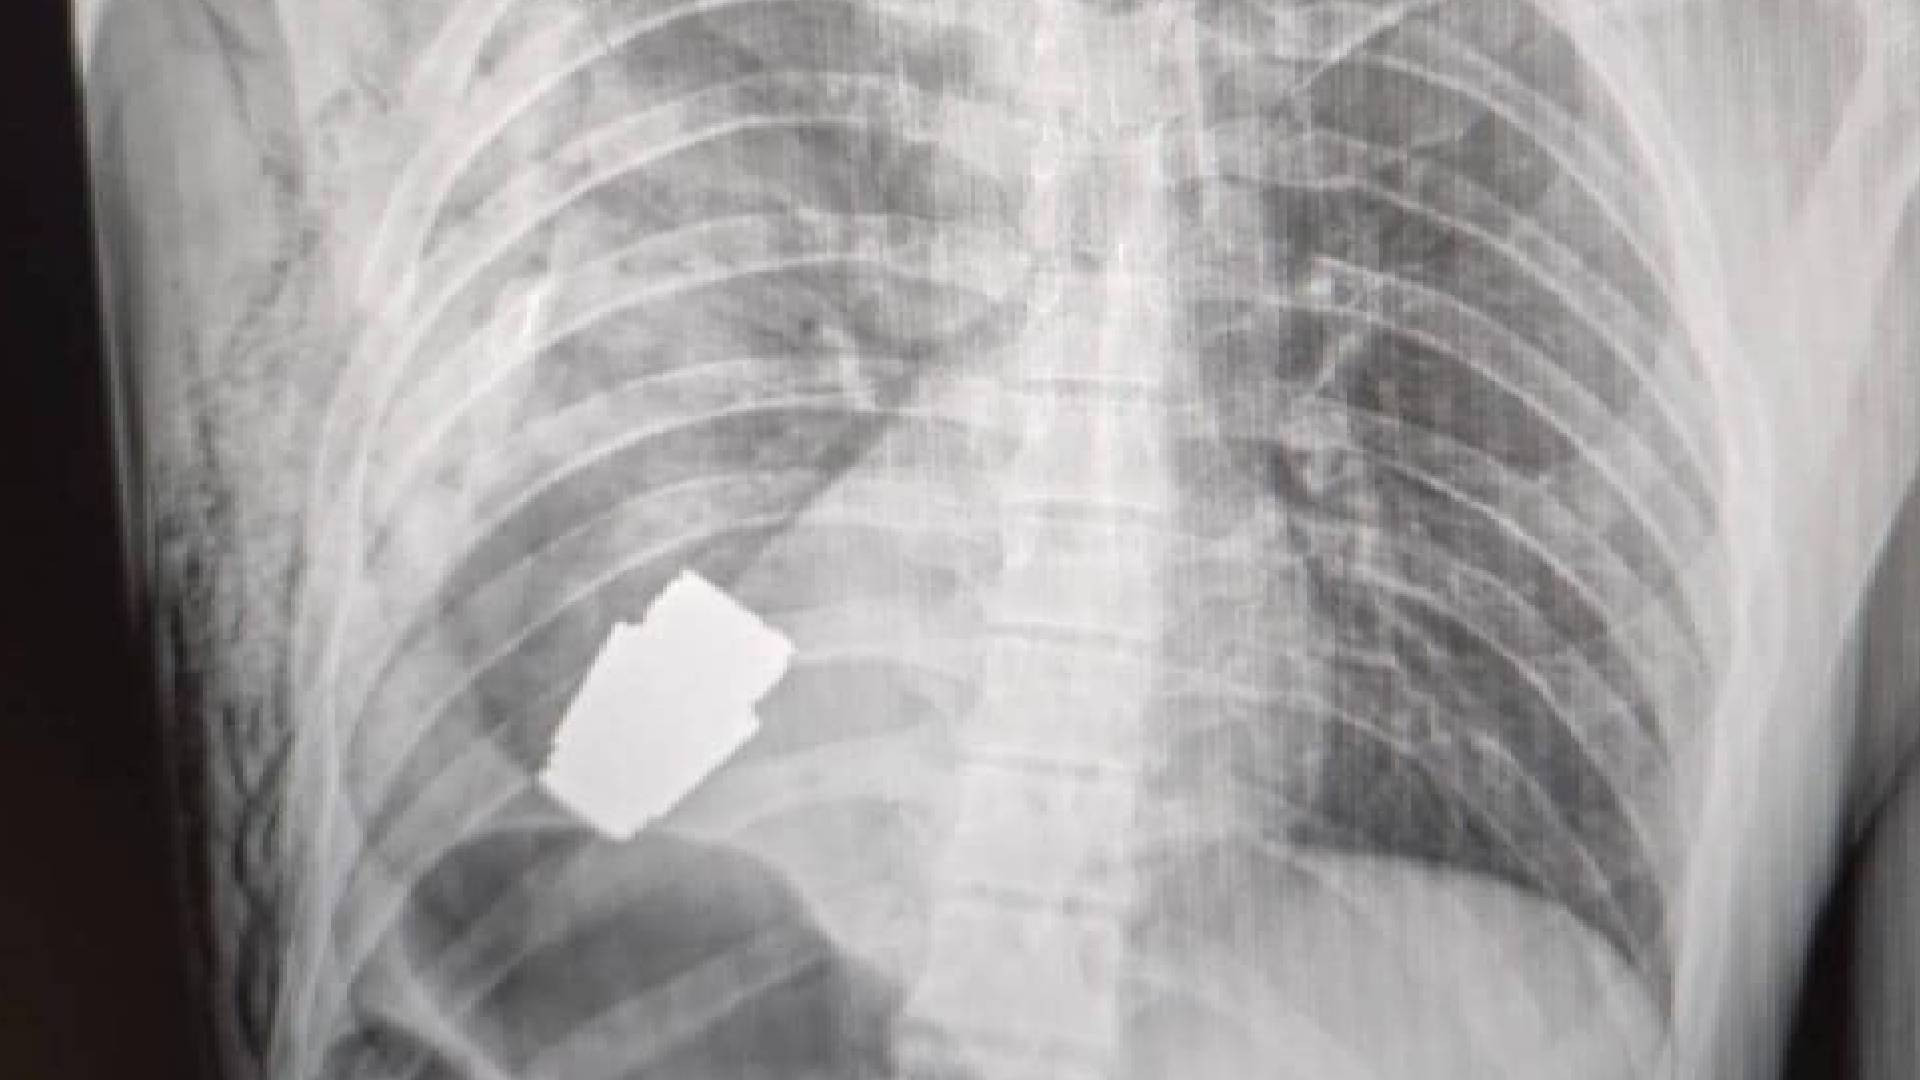

Гранаты после операции

Гранаты после операции 114 фотографий